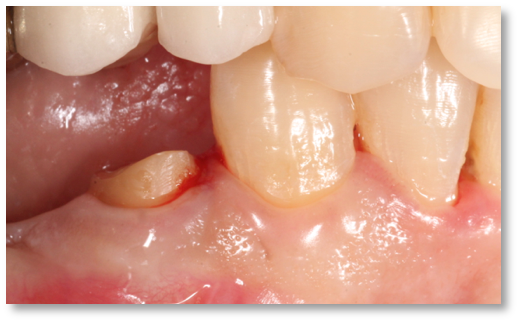

![]() | ![]() |

| Free gingival graft surgery’ to thicken gum and prevent further recession | Gum recession surgery in an aesthetic site |